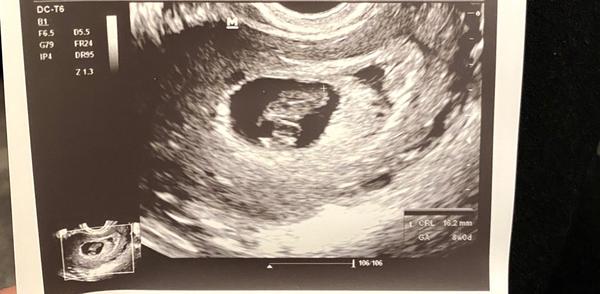

9. týden těhotenství. Odpovídá tomu velikost plodu?

myslíte, že by takhle odpovídal plod 8+0?

(6+0 od početí) nebo je to 8 týdnů od početí?

Sedí reálné měření s výpočtem gestačního stáří?

ano, tak jak je psáno na fotce - CRL (temeno-kostrční délka plodu) je 16,2 mm, což odpovídá 8+0. Vždy bývá myšleno tzv. menstruační stáří, tj. od prvního dne poslední menstruace. Skutečné stáří embrya je o 2 týdny méně, tj. jak píšete ve Vašem případě 6+0 od početí.